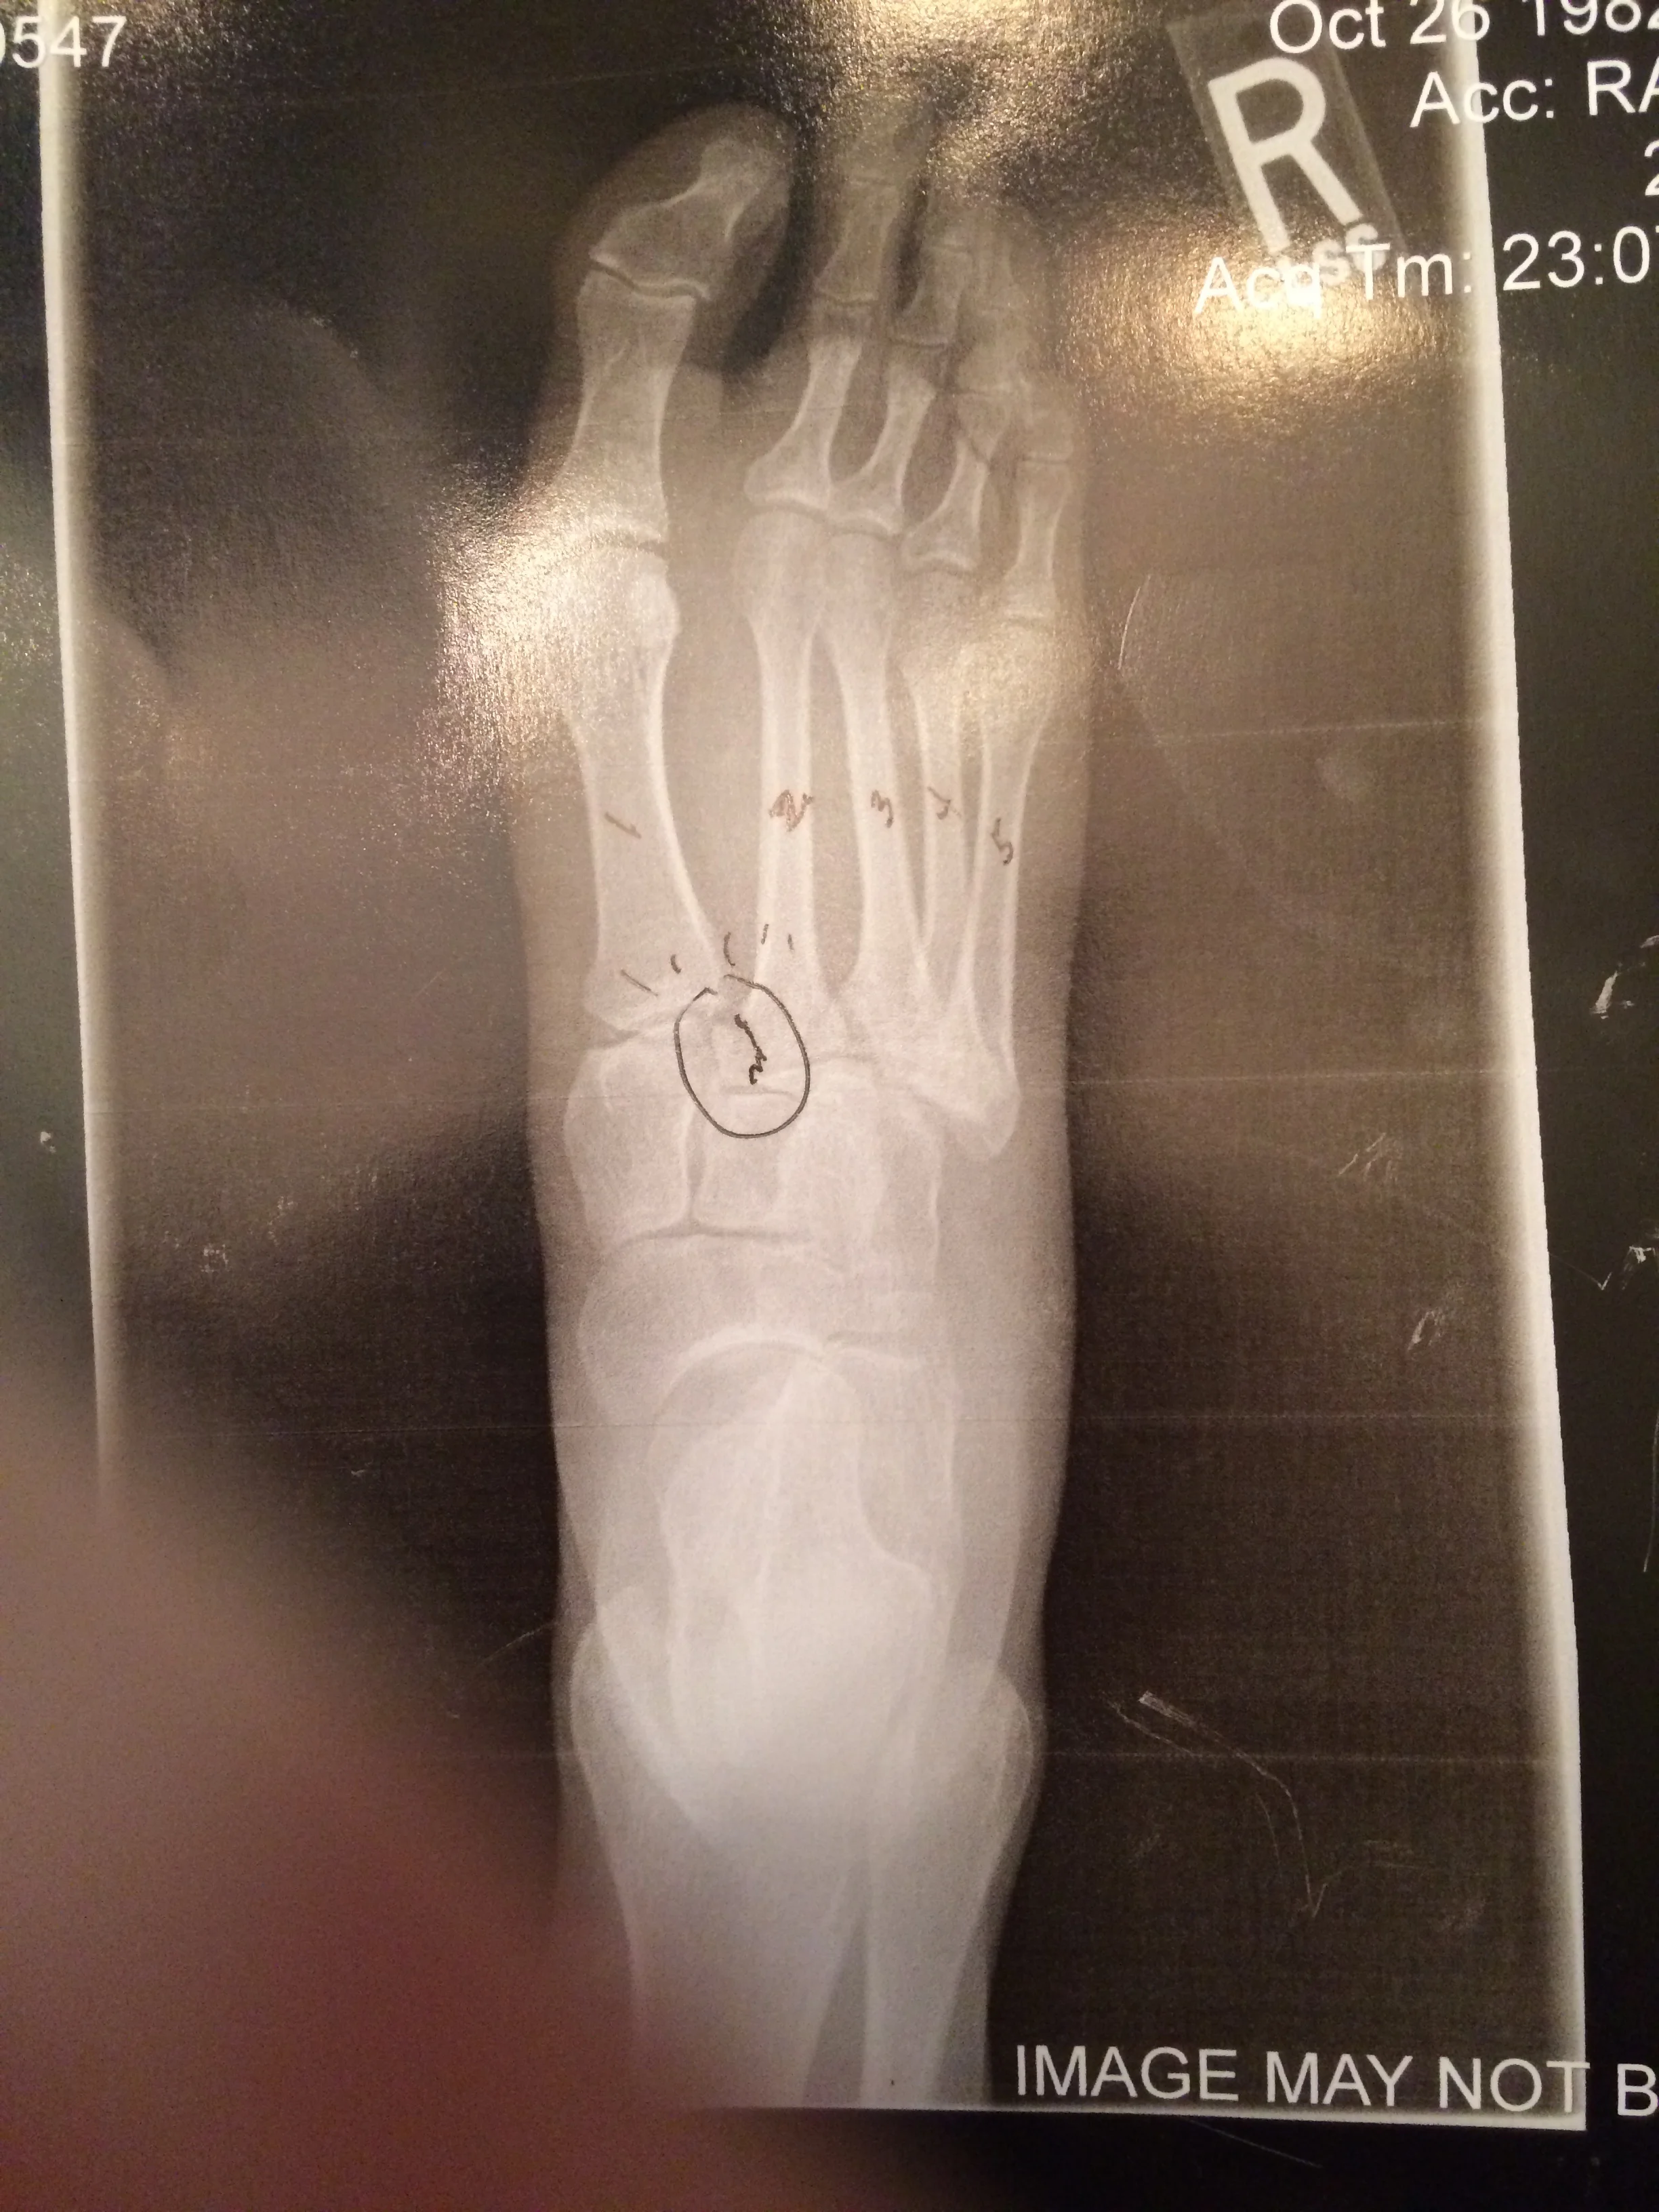

I've got a list of activities I want to do now that we're living in California: learn to SUP and surf, hike the numerous trails, play beach volleyball, and longboard around the neighborhood with my dog. So, I bought a longboard...and subsequently suffered a Lisfranc fracture and will be undergoing surgery tomorrow to have a plate and 4 screws inserted into my right foot. YIKES! More on that in a minute...

After my diagnosis, I researched as much as I could on Lisfranc injuries, especially after meeting with the doctors and hearing that my foot will never be the same again. I'll be in a cast, unable to bear any weight (aka still on crutches) for approximately 10 weeks after surgery, followed by many, many PT sessions to regain function of my foot and ankle. Full recovery takes at least a year, but it will never be 100%. That's terrifying to hear, especially when you rely on your feet so much. There's a possibility I won't be able to run again, that just walking more than a mile will be extremely painful. I wanted to cry right then and there in front of the doctor as he answered my questions. It consumed my thoughts for a whole week, and that was as long as I would allow it. Instead of feeling sorry for myself, being depressed and upset, I've made a conscious effort to keep moving forward.